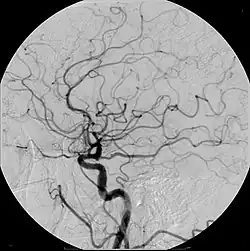

Iodinated contrast contains iodine. It is the main type of radiocontrast used for intravenous administration. Iodine has a particular advantage as a contrast agent for radiography because its innermost electron ("k-shell") binding energy is 33.2 keV, similar to the average energy of x-rays used in diagnostic radiography. When the incident x-ray energy is closer to the k-edge of the atom it encounters, photoelectric absorption is more likely to occur. Its uses include:

- Angiography (arterial investigations)